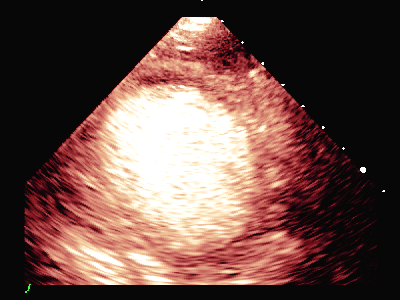

MCE:

动态图(2)静息状态双平面LVO

负荷前左室壁未见明确节段性运动异常,左室各节段心肌灌注充盈良好。

平板负荷量达89%时,该时患者心率157次/分,出现短阵性室性心动过速,即刻超声造影检查显示:负荷后左室前间隔中段、室间隔心尖段、侧壁中段、心尖段、下壁心尖段、前壁心尖段及心尖帽运动减弱。室间隔心尖段及心尖帽心肌灌注稀疏。

患者休息后检查:左室壁未见明确节段性运动异常,左室各节段心肌灌注充盈良好。